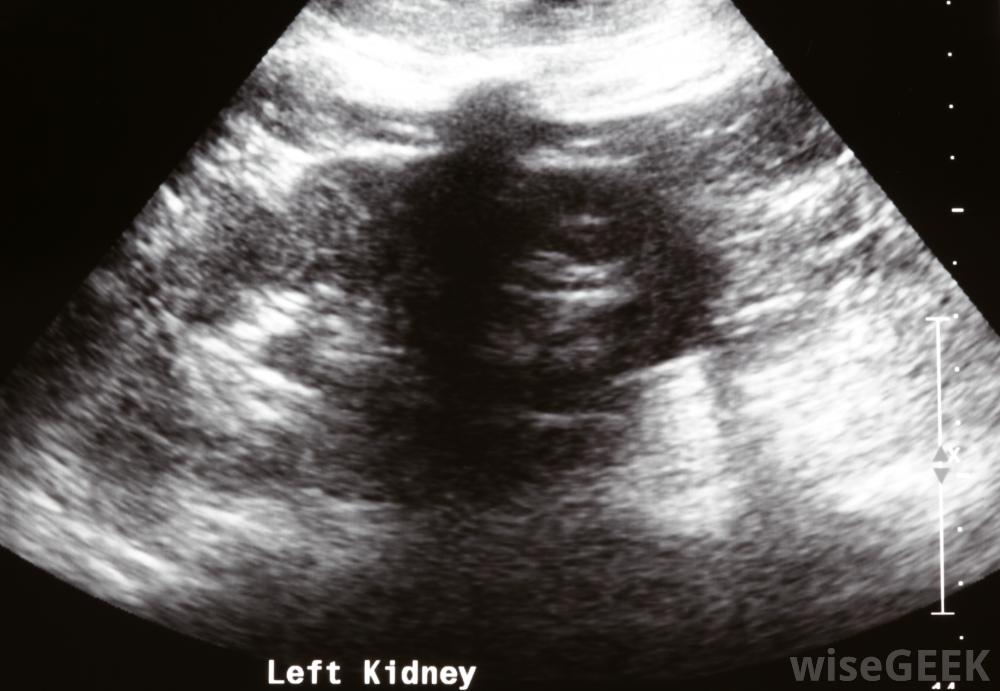

低回声病变是一种在超声检查中可以看到的异常区域,因为它比周围的组织暗。这种异常可以在身体的任何地方发展,并不一定意味着癌症。血液检查,活检,可能需要进一步的放射学研究来确定低回声病变的成分,有时简称为病变。 可...

在超声波检查中,技术人员将一种被称为传感器的手持设备应用于需要评估的身体部位。传感器发出高频声波,当它们接触内部结构时,这些声波会反射回设备。监视器上会形成黑白图像,根据回声的强度,放射科医生称来自高反射表面的较亮图像

高回声,而反射较弱的区域则显示为较暗的区域,并被称为

低回声

在超声检查过程中,技术人员将一种称为传感器的手持设备应用于身体以评估肾脏。